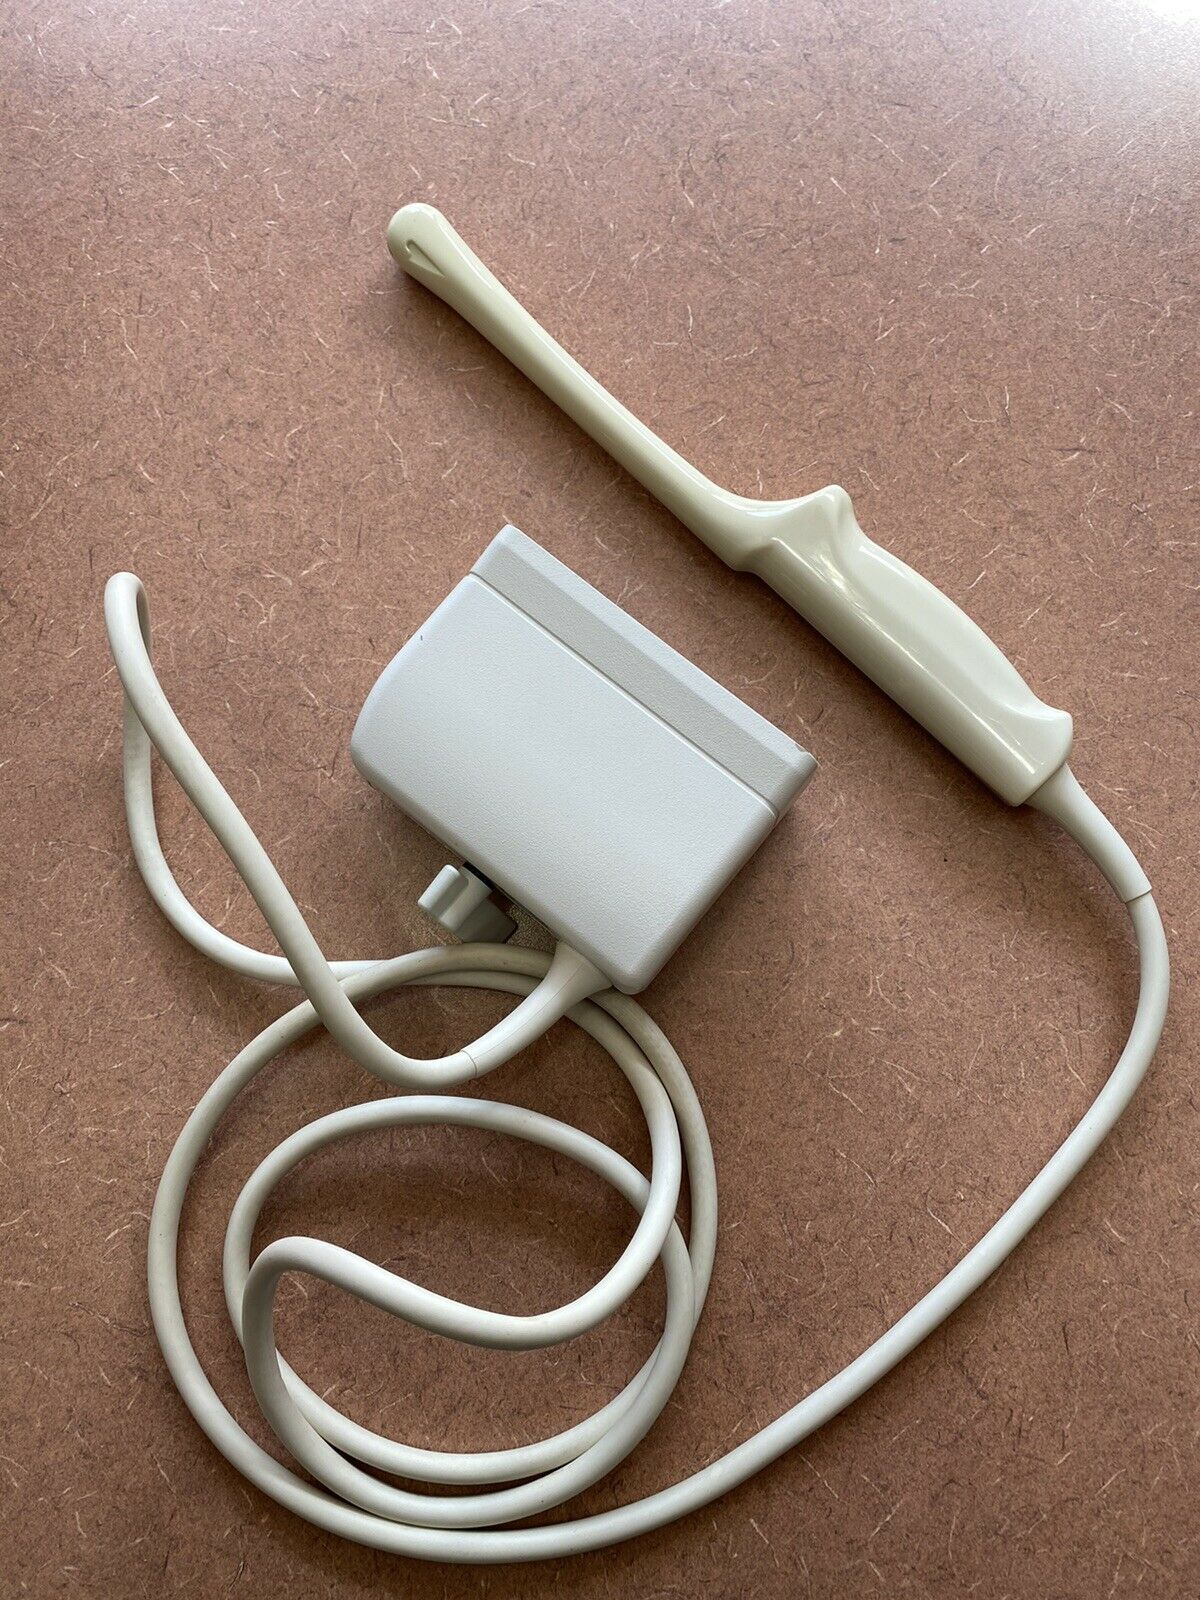

PHILIPS ULTRASOUND TRANSDUCER S4-1 PROBE

Sale price$ 1,228.36